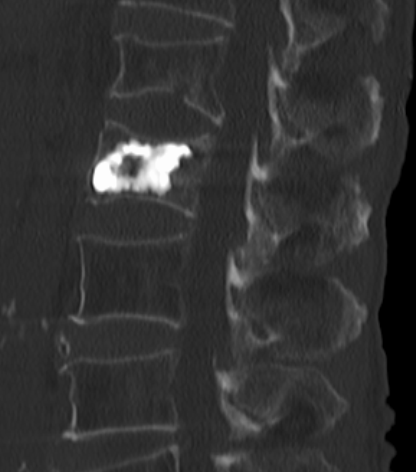

十余年来,我科室相继开展骨质疏松症的相关诊治工作,逐渐形成了自身的诊治体系,后经过整合联系,形成了以骨科二病区为龙头,联合检验科、放射科、内分泌科、血液风湿科等多学科结合、内外协作的骨松诊治MDT模式。目前采用的诊断方式有血钙及维生素ADKE检测、双能X线骨密度检测等,治疗方面也内外兼修,既可应用促成骨的四烯甲萘醌等,抑制骨吸收的唑来膦酸等药物治疗,又可采取椎体强化术、经皮穿刺椎弓根钉置入术等有效手术治疗,可结合患者自身情况,采取合适的治疗手段。开展骨质疏松诊治工作的十几年来,遵循指南,结合当地实际,总结归纳出了一套立足自身实际的诊疗体系,采取药物治疗与手术治疗相结合、因人而宜、综合施治的个体化的综合诊疗方案等。近年来,随着微创理念的推行和ERAS理念的实践,骨科二病区率先在本地区开创性的应用微创经椎间孔入路椎体强化术、经皮穿刺椎弓根钉置入术等先进治疗手段,实现立竿见影的治疗效果,深得广大患者的好评,取得了良好的社会效益和学术影响力,使桓台百姓足不出县即可享受到国内外先进的脊柱外科诊治体验。

术后术前